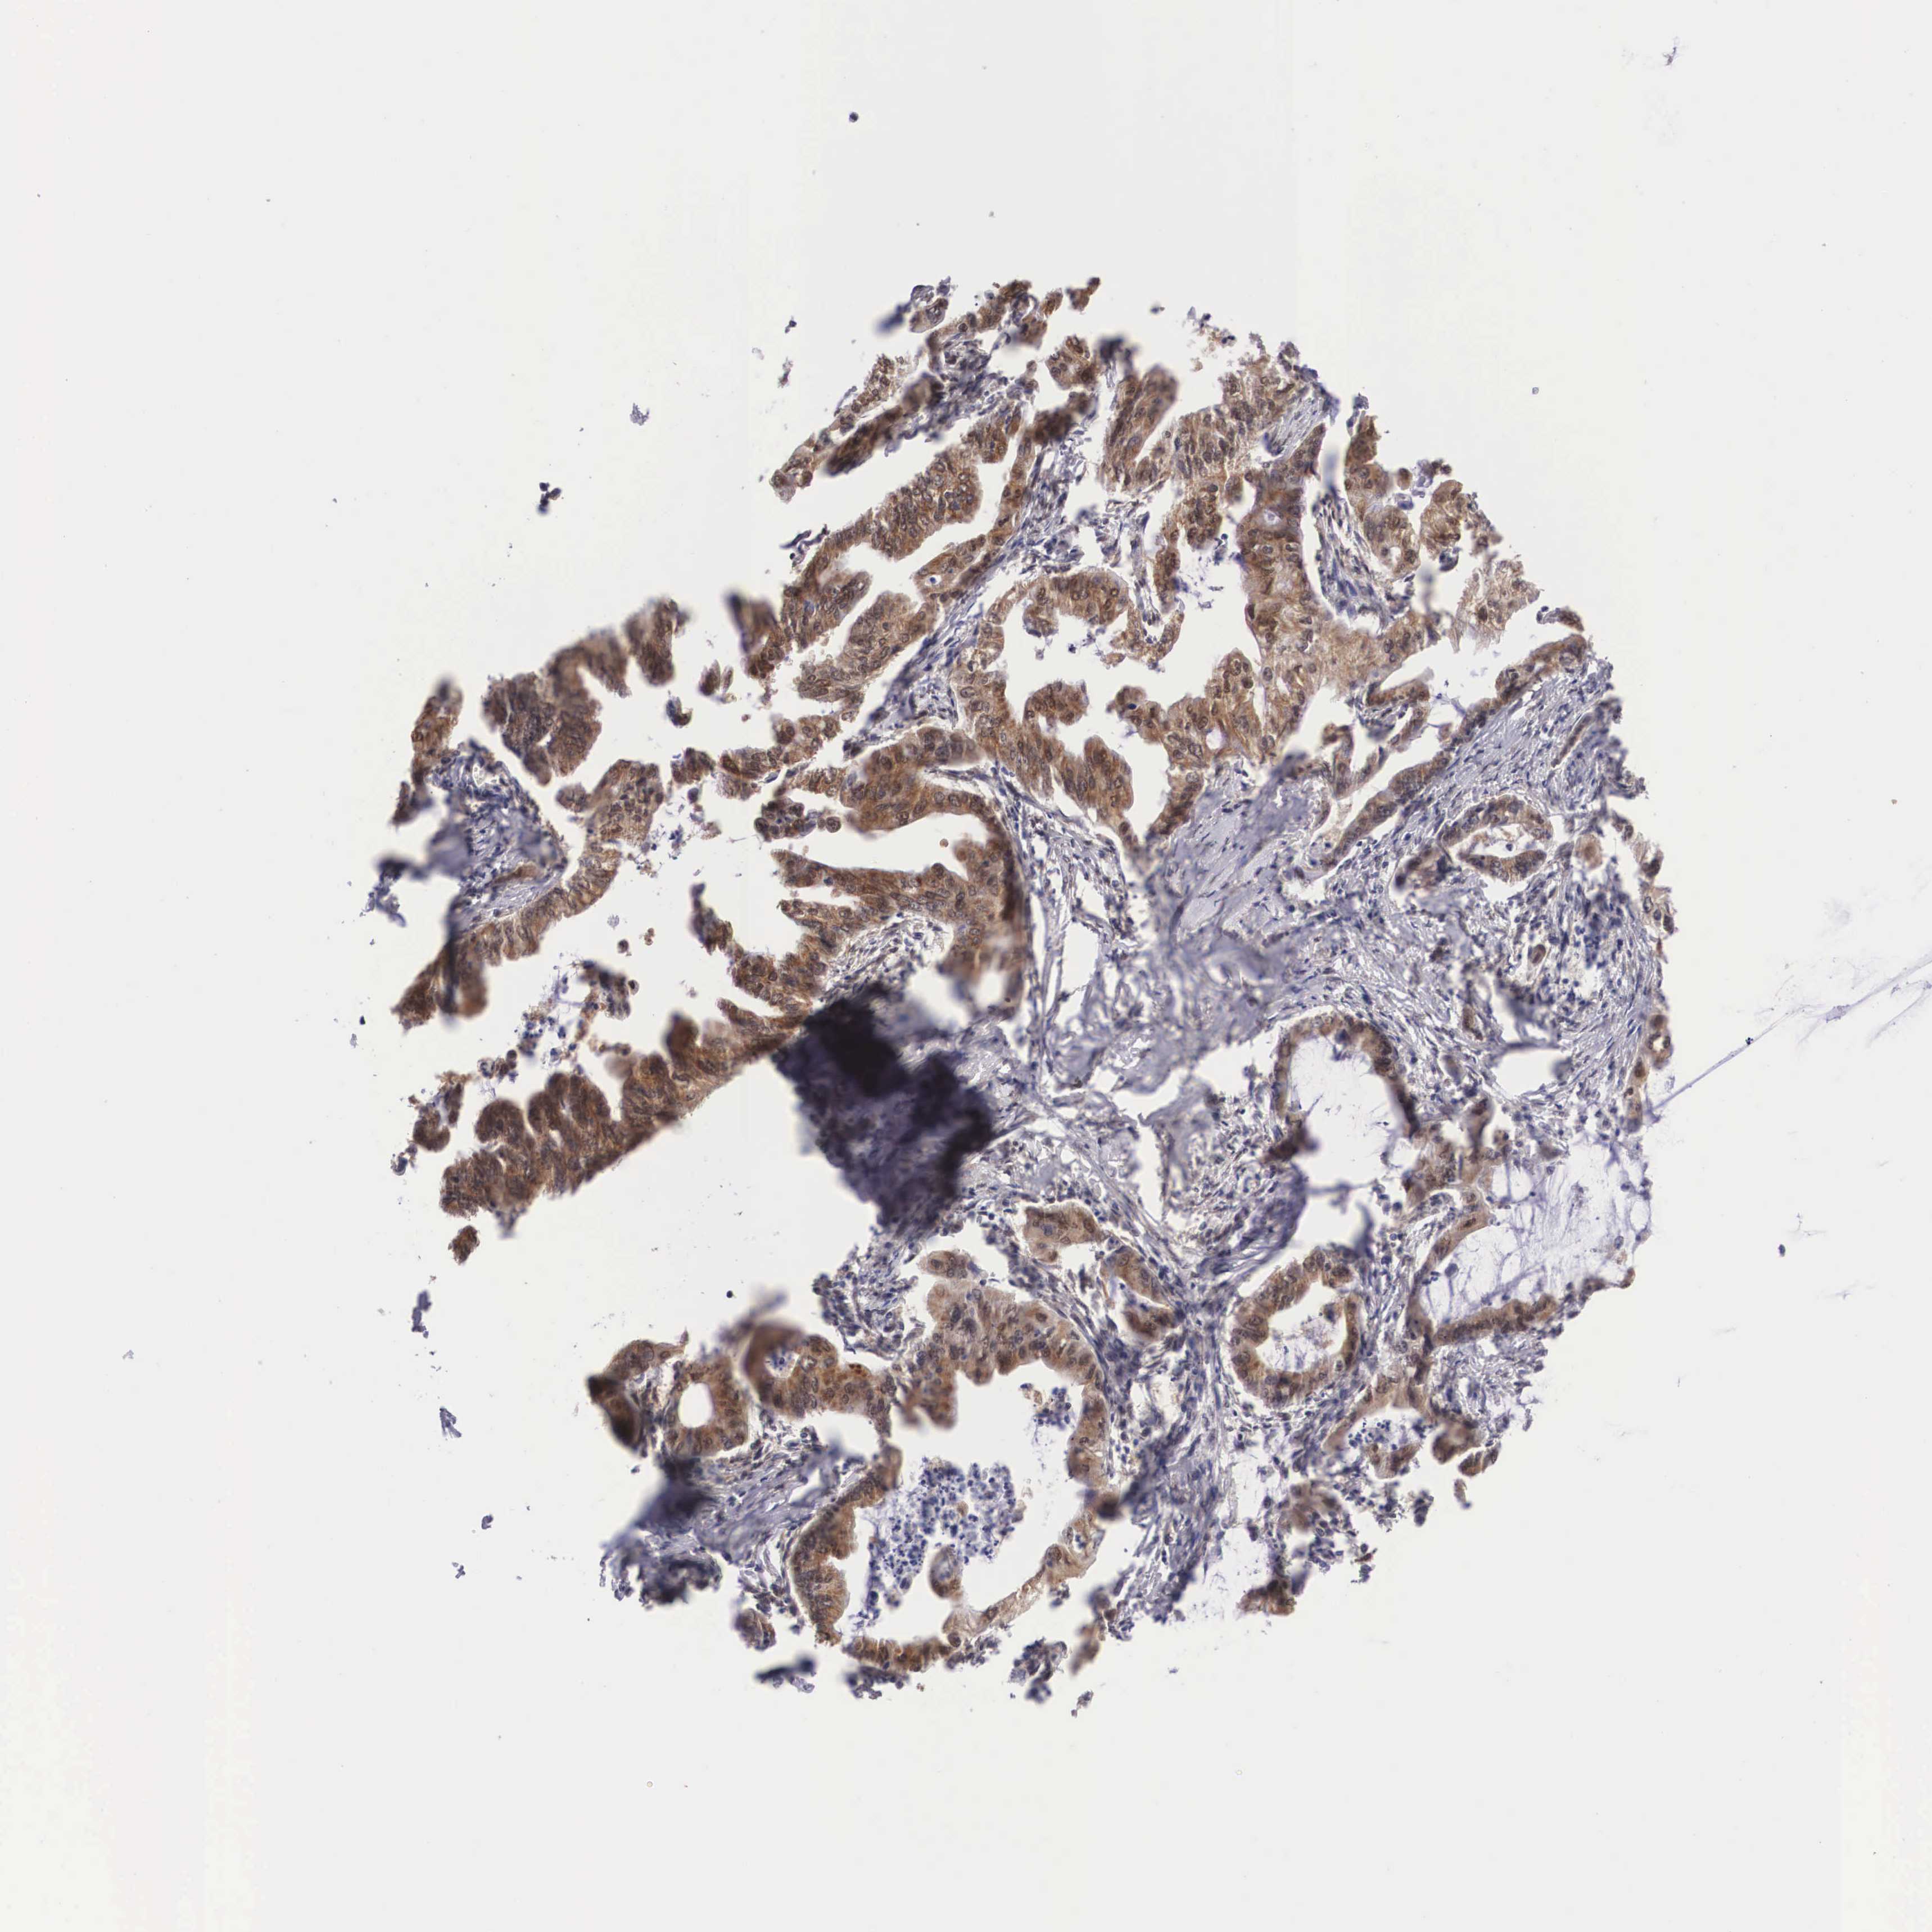

STOMACH CANCER - Protein expressioni

A mouse-over function shows sample information and annotation data. Click on an image to view it in a full screen mode. Samples can be filtered based on level of antibody staining by selecting one or several of the following categories: high, medium, low and not detected. The assay and annotation is described here.

Note that samples used for immunohistochemistry by the Human Protein Atlas do not correspond to samples in the TCGA dataset.

Antibody stainingi

Antibody staining in the annotated cell types in the current human tissue is reported as not detected, low, medium, or high, based on conventional immunohistochemistry profiling in selected tissues. This score is based on the combination of the staining intensity and fraction of stained cells.

Each image is clickable and will lead to virtual microscopy that enables deeper exploration of all samples and also displays staining intensity scores, fraction scores and subcellular localization as well as patient and tissue information for each sample.

Antibody HPA000633

Staining

High

Medium

Low

Not detected

Intensity

Strong

Moderate

Weak

Negative

Quantity

>75%

75%-25%

<25%

None

Location

Nuclear

Cytoplasmic/membranous

Cytoplasmic/membranous,nuclear

Adenocarcinoma, NOS